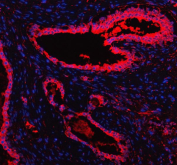

Immunofluorescent staining of FFPE human prostate cancer tissue with MARS1 antibody (red) and DAPI nuclear stain (blue). HIER: steam section in pH8 EDTA buffer for 20 min.